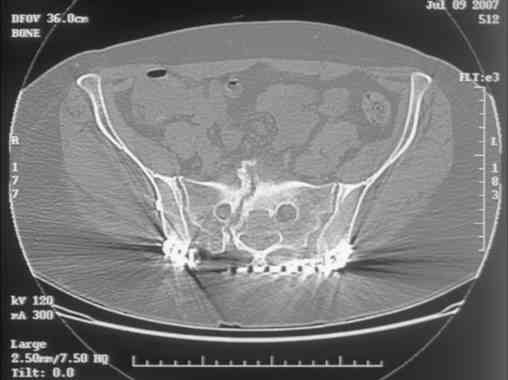

Re: Sacral Non-Union

Here is a magnified view. Sorry about the quality but the CT was scanned into our system.